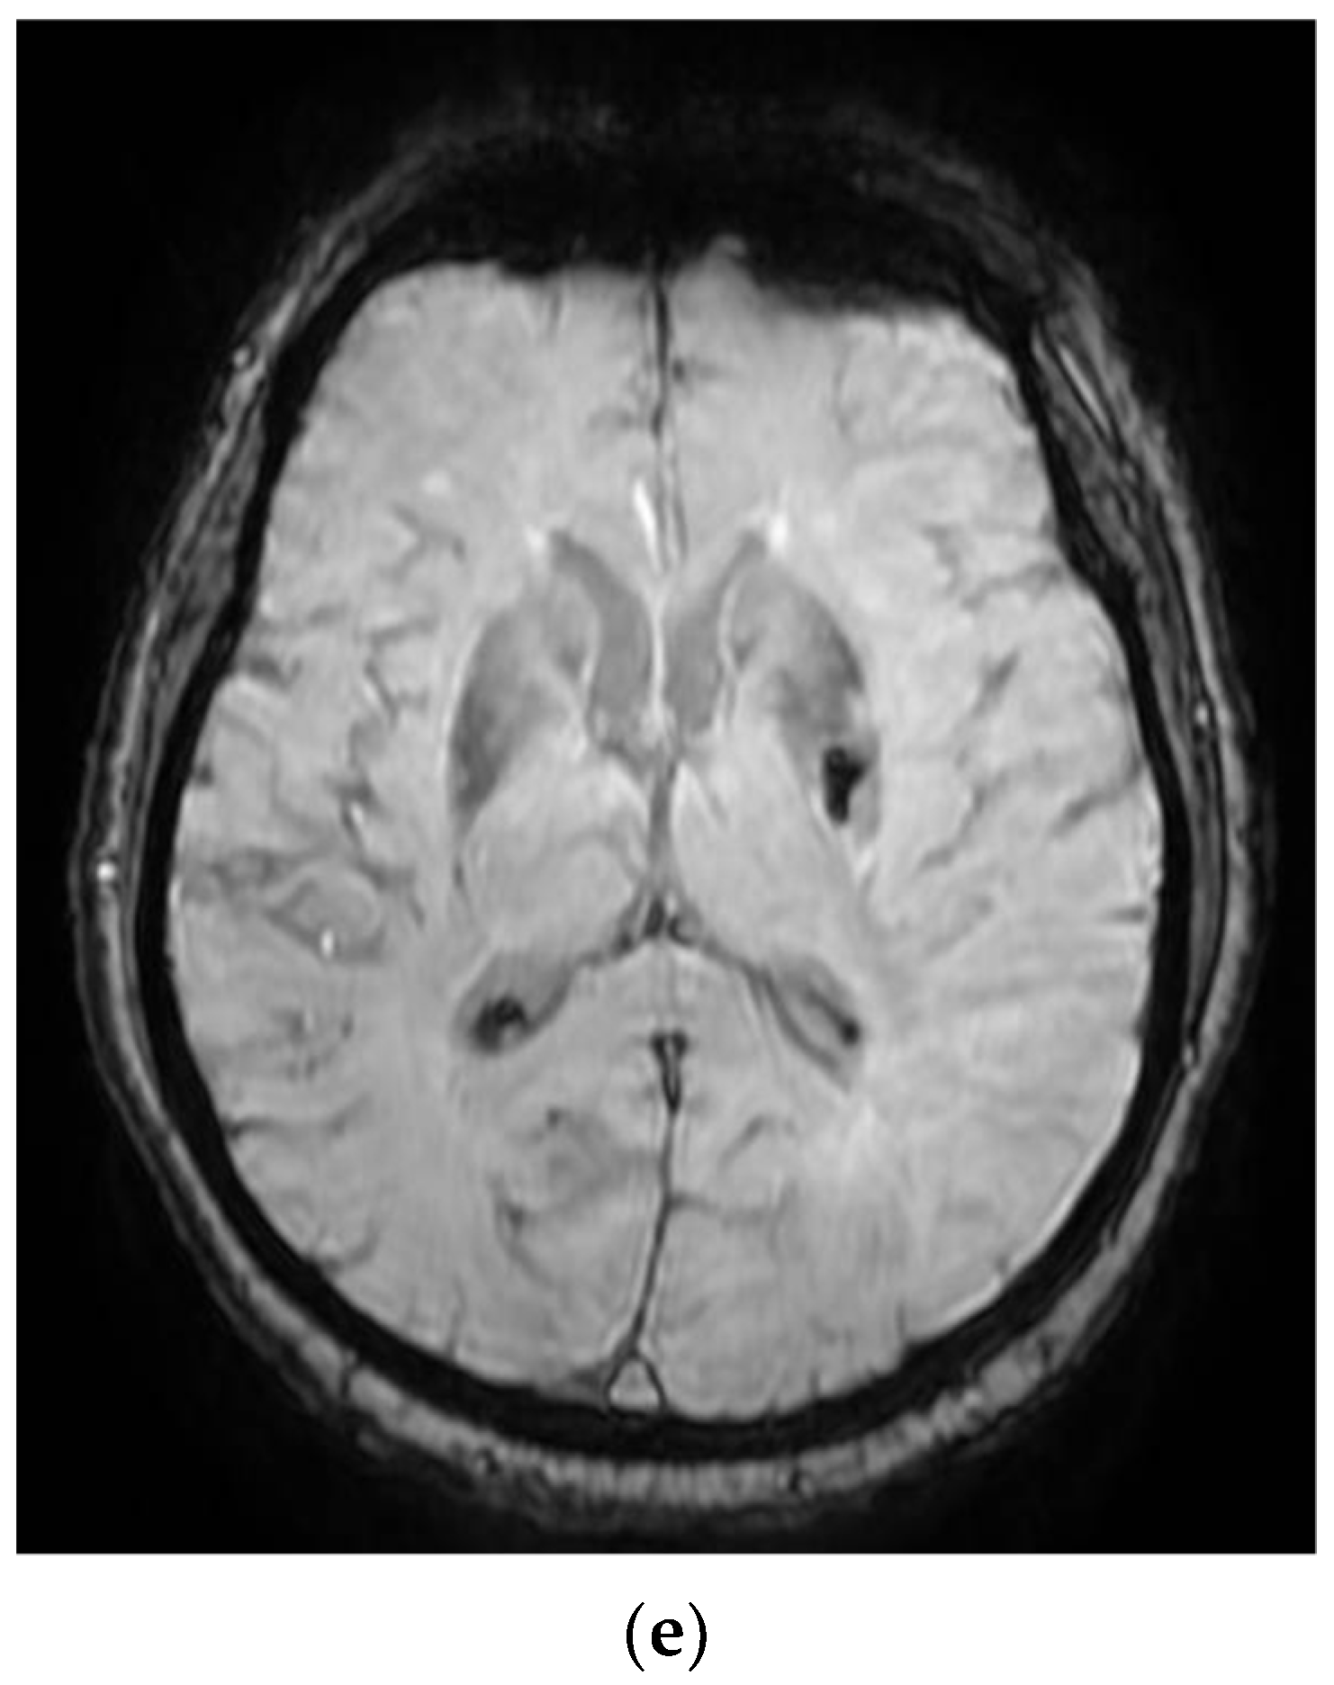

Figure 2. MRI images of the Case 2 patient shows extended foreshores, irregularly delimited, T2-FLAIR hyperintense (a,b), with restriction of marked diffusion (c,d), confirmed by a hypointense signal on the map of apparent diffusion (d), situated in the cortical–subcortical frontal–parietal–occipital and left insular part, with capsular and lenticular extension. Centimetric intralesional focal signal point SWAN sequence was associated in the left lenticular nucleus (e). These characteristics are suggestive of acute ischemic stroke on the left superficial and profound Sylvian territory, and on the superficial territories of the border between the median cerebral artery/posterior cerebral artery and medium cerebral artery/left anterior cerebral artery (ad), with a small area of hemorrhagic transformation in the lenticular nucleus (e).

On admission, the patient had a brain CT scan, which showed acute ischemic stroke in the left MCA with an ASPECTS score of 9 points. On day 2 of hospitalization, the patient underwent a brain MRI, which showed acute ischemic stroke in the superficial and deep left Sylvian territories, in the superficial border territories of the middle cerebral artery/posterior cerebral artery, and in the middle cerebral artery/left anterior cerebral artery, with a small area of hemorrhagic transformation in the lenticular nucleus (Figure 2). On day 7 of hospitalization, the patient developed a cough with mucopurulent sputum, became trachea–bronchial loaded, and was tested by RT-PCR for SARS-CoV-2, with the result being positive. The patient was transferred to a hospital for supporting COVID-19.